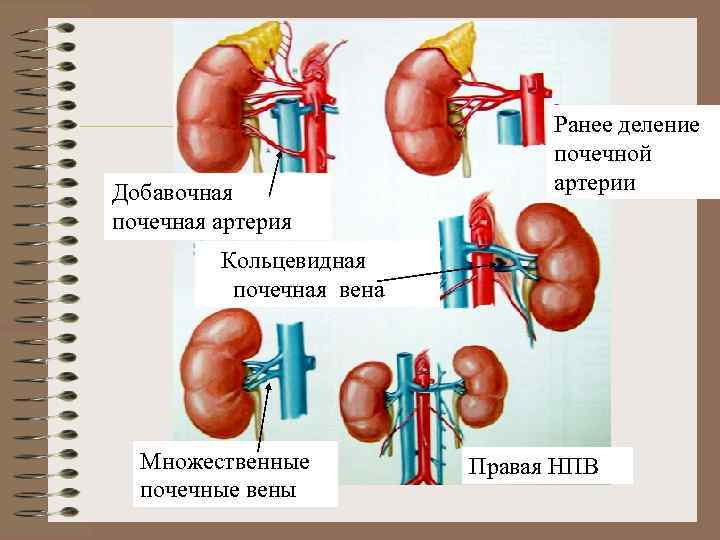

Аномалии почечных артерий 1. Аномалии положения и количества почечных артерий • Агенезия почечной артерии • Гипоплазия почечной артерии • Добавочная почечная артерия • Двойная почечная артерия • Множественные артерии 2. Аномалии формы и структуры артериальных стволов • А. аневризма почечных артерий • Б. фибромускулярный стеноз • В. Артерио-венозные фистулы

Аномалии почечных вен • А. аномалии правой почечной вены (множественные вены, впадение яичковой вены в почечную) • Б. аномалии левой почечной вены кольцевидная вена, ретроаортальная, экстракавальное впадение

Добавочная почечная артерия Ранее деление почечной артерии Кольцевидная почечная вена Множественные почечные вены Правая НПВ